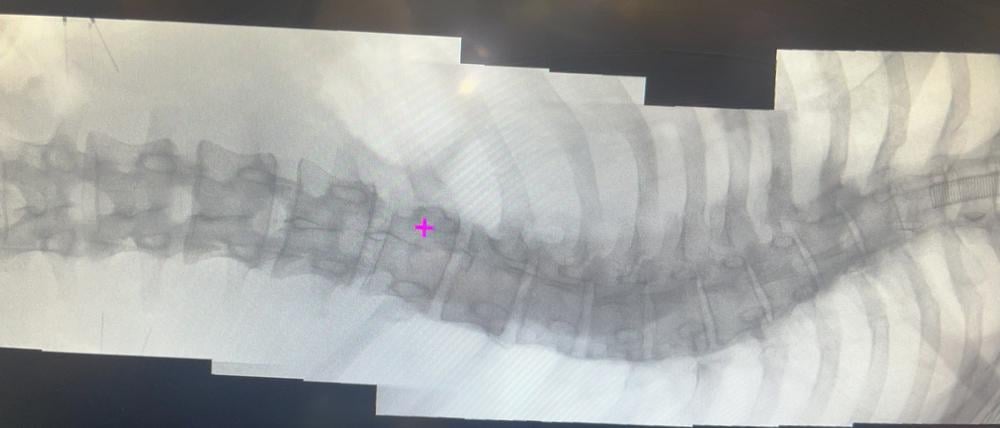

Zehn Stunden schneiden, hämmern und schrauben: Dane bekommt eine gerade Wirbelsäule

Etwa zwei Prozent der Bevölkerung leiden unter einer Verkrümmung der Wirbelsäule, der sogenannten Skoliose. So auch der 21-jährige Dane Storch. Wir waren live dabei, als er in Berlin operiert wurde.